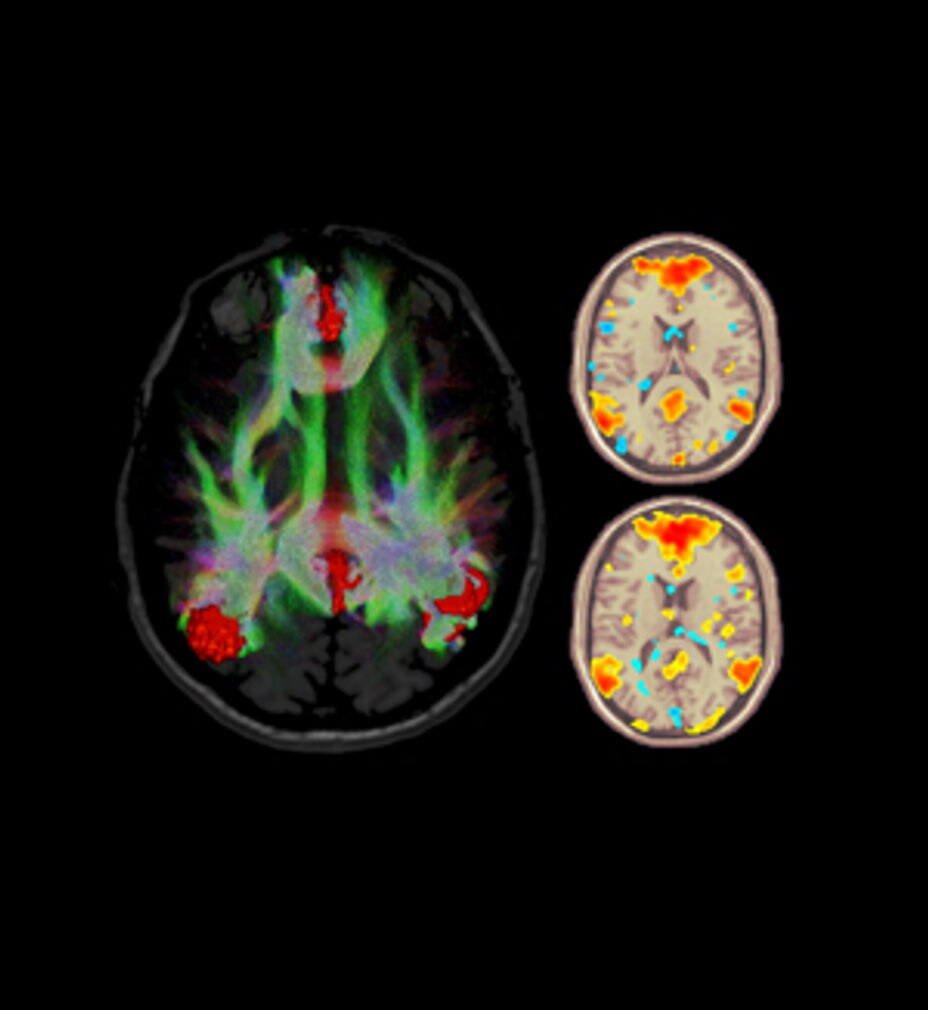

cNERVE

Acompanhe procedimentos de bloqueio de nervos com cNerve

Ajuda a detectar e acompanhar nervos em 99% dos casos durante escaneamento ativo ou ao revisar um clipe armazenado³ enquanto também exibe um mapa de distribuição das áreas do corpo impactadas pelo procedimento de bloqueio de nervos selecionado.

Novas Fronteiras no Ultrassom Point of care: Levando IA a Bloqueios de Nervos

Siga o Dr. Bernard Victor Delvaux, Anestesista, para o mundo de inteligência artificial para POCUS conforme sua colaboração com Doron Shaked, Cientista de Dados, ganha vida prestando suporte para a confiança clínica em bloqueios de nervos.